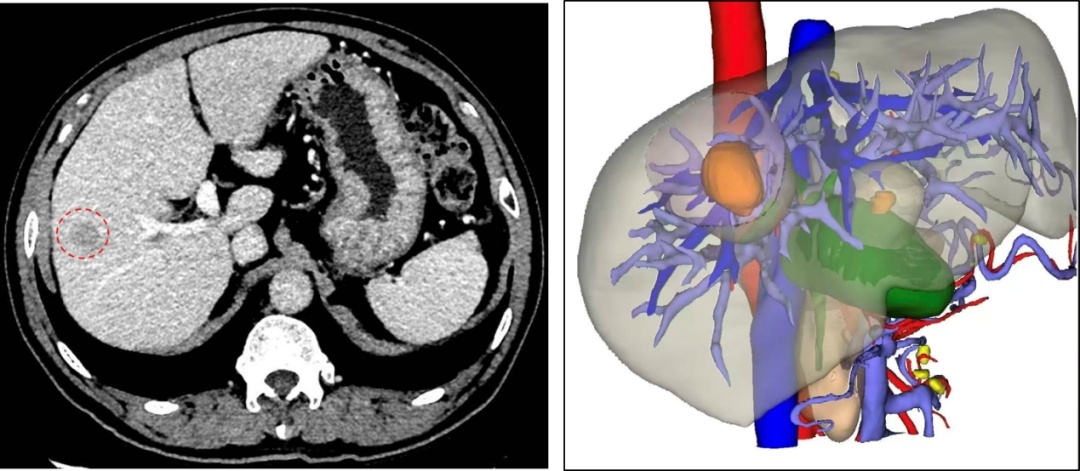

术前MR检查

术前三维重建

陈伯的肿瘤长在肝脏S8段,这个位置被外科医生称为“肝脏的穹顶”,深藏于膈肌之下,紧邻重要的肝内血管,手术视野暴露和操作空间都极其有限。加上患者高龄,心肺功能代偿能力弱,麻醉与手术风险呈几何级数增加。

“手术不易,但我们必须迎难而上。”蒋小峰教授说。面对挑战,医院迅速启动了多学科协作(MDT)机制。麻醉科团队为陈伯量身定制了精细的循环管理与肺保护策略;医学影像科通过三维重建技术,将肿瘤与血管的立体关系清晰地呈现出来,犹如一份精准的“作战地图”;呼吸内科、心血管内科专家则对陈伯的全身状况进行了充分评估与优化。

经过周密的准备,手术如期进行。术中运用了肝胆外科的特色技术——腹腔镜超声对肿瘤进行精准定位识别,并结合术中荧光染色实现肝段边界的清晰显影,从而辅助规划精准切除范围。在高清腹腔镜的放大视野下,蒋小峰教授操纵着精细的器械,在方寸之地稳健操作。借助这些先进技术的引导,他巧妙避开重要血管和胆管,如同进行一场精密的“肝脏雕刻”,最终完整切除肿瘤,并最大限度保留健康肝组织。手术过程出血极少,患者生命体征始终保持平稳。